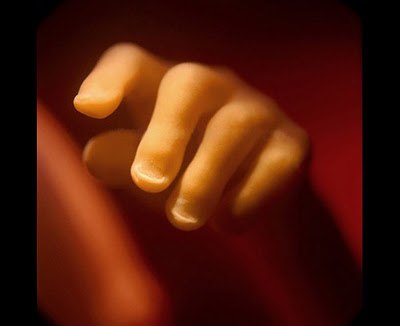

Эволюция эмбриона на фотографиях Леннарта Нильсона — шведского фотографа и ученого, пионера медицинской фотографии. Он потратил 10 лет жизни, чтобы снять на пленку эволюцию эмбриона от зачатия до рождения. Уникальные кадры с места, откуда люди делают перв10 写真